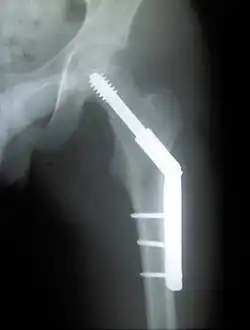

Fracture supported by dynamic hip screw

A trochanteric fracture, below the neck of the femur, has a good chance of healing.

Closed reduction may not be satisfactory and open reduction then becomes necessary.[43] The use of open reduction has been reported as 8-13% among pertrochanteric fractures, and 52% among intertrochanteric fractures.[44] Both intertrochanteric and pertrochanteric fractures may be treated by a dynamic hip screw and plate, or an intramedullary rod.[43]

The fracture typically takes 3–6 months to heal. As it is only common in elderly, removal of the dynamic hip screw is usually not recommended to avoid unnecessary risk of second operation and the increased risk of re-fracture after implant removal. The most common cause for hip fractures in the elderly is osteoporosis; if this is the case, treatment of the osteoporosis can well reduce the risk of further fracture. Only young patients tend to consider having it removed; the implant may function as a stress riser, increasing the risk of a break if another accident occurs.